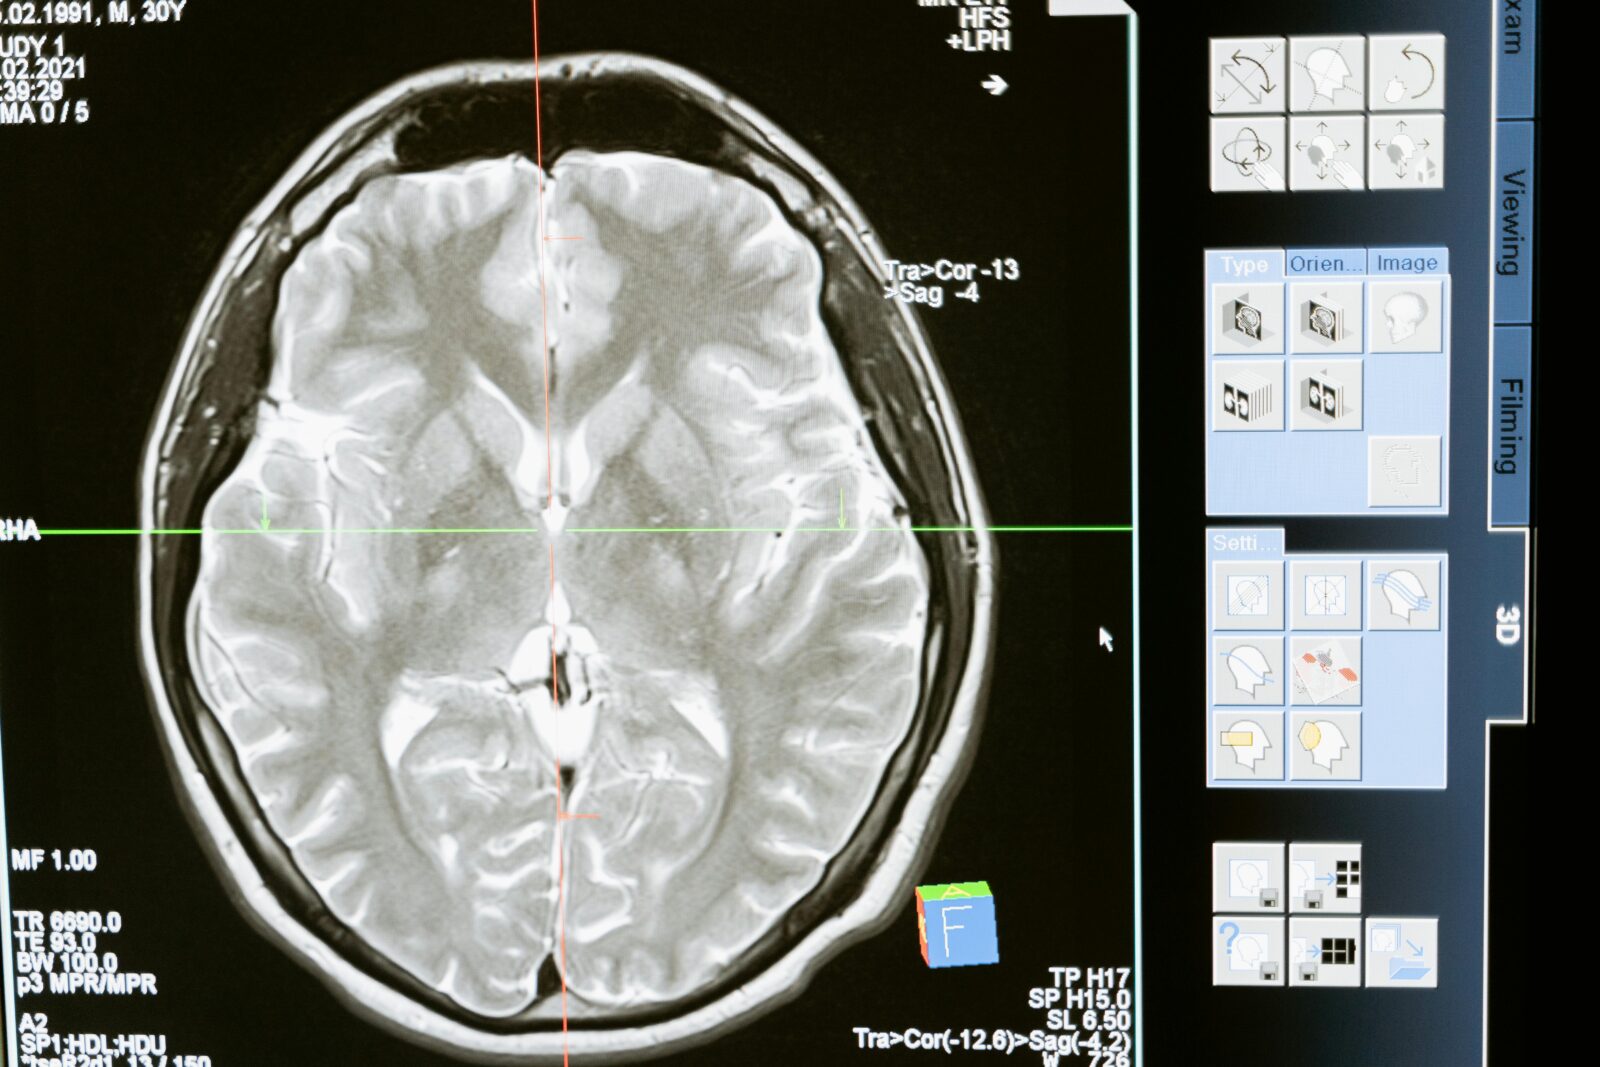

ilustrační foto